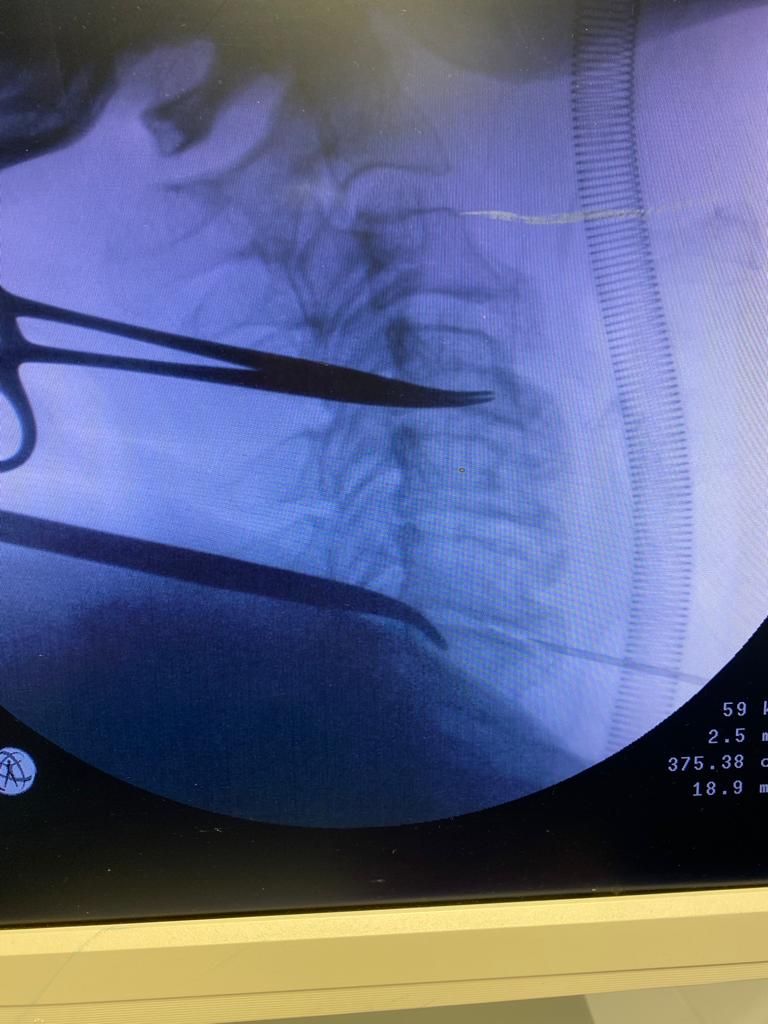

Nelle foto si può vedere un intervento di asportazione di ernia cervicale che ha causato nella paziente una perdita di forza della mano fortemente debilitante. L'intervento è stato eseguito presso il centro chirurgico toscano in convenzione con il sistema sanitario nazionale. La paziente sta gradualmente migliorando anche grazie alla fisioterapia. La scelta di un intervento chirurgico equivale ad intraprendere di un percorso che inizia dalla prima visita ambulatoriale e che prosegue con i successivi follow up. Lungo questo percorso il chirurgo e il paziente camminano insieme affrontando le stancanti salite e le successive discese per raggiungere gli obiettivi fissati nel primo incontro.